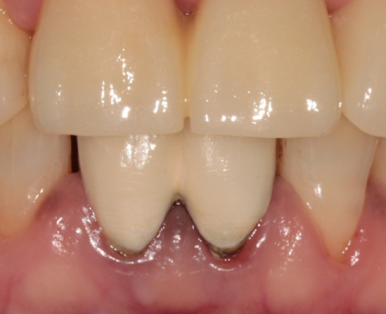

남아 있는 앞니의 신경치료를 안전하게 마무리 한 모습

이후 보철 과정을 진행하였고,

다음과 같이 치료가 마무리되었습니다.

환자분께서는 치료 전 보철물보다 훨씬 예쁘다고 만족하셨네요.

좌측 2024. 1 - 우측 2024. 3